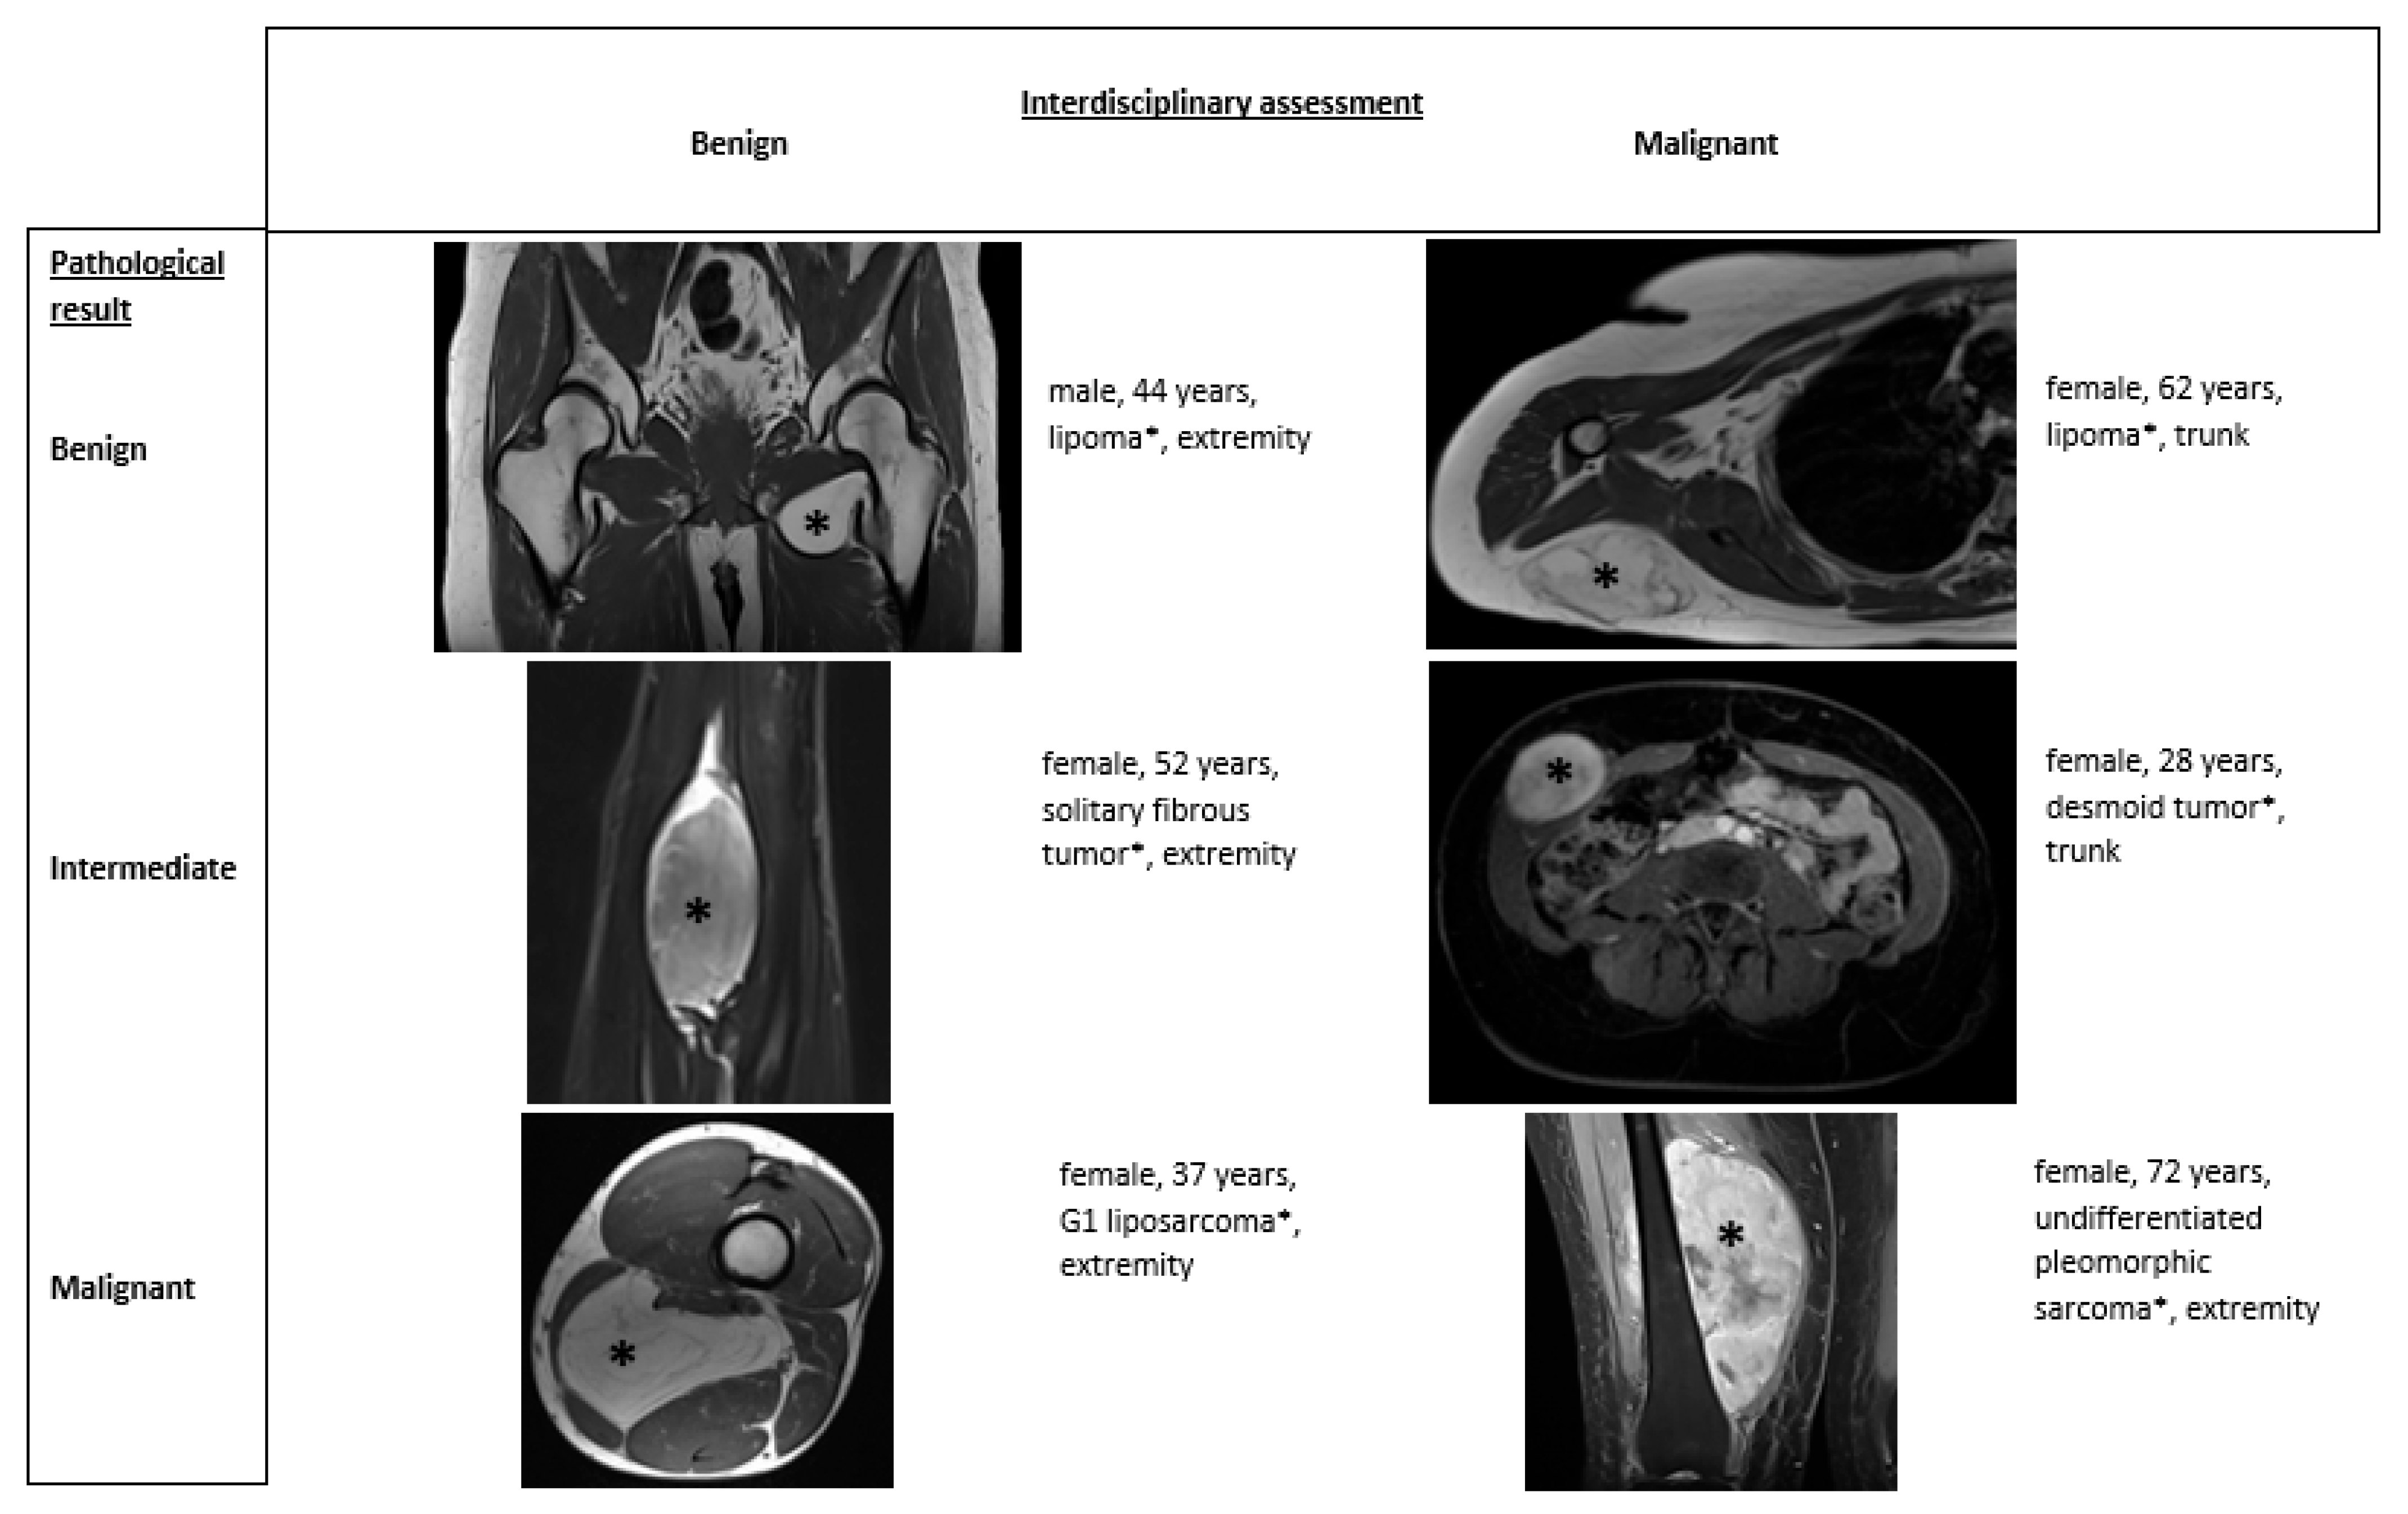

Figure 2 shows examples of different tumor types and the correlation between multidisciplinary assessment and pathological results.

Figure 2.

Different tumor types with multidisciplinary assessment and pathological result.